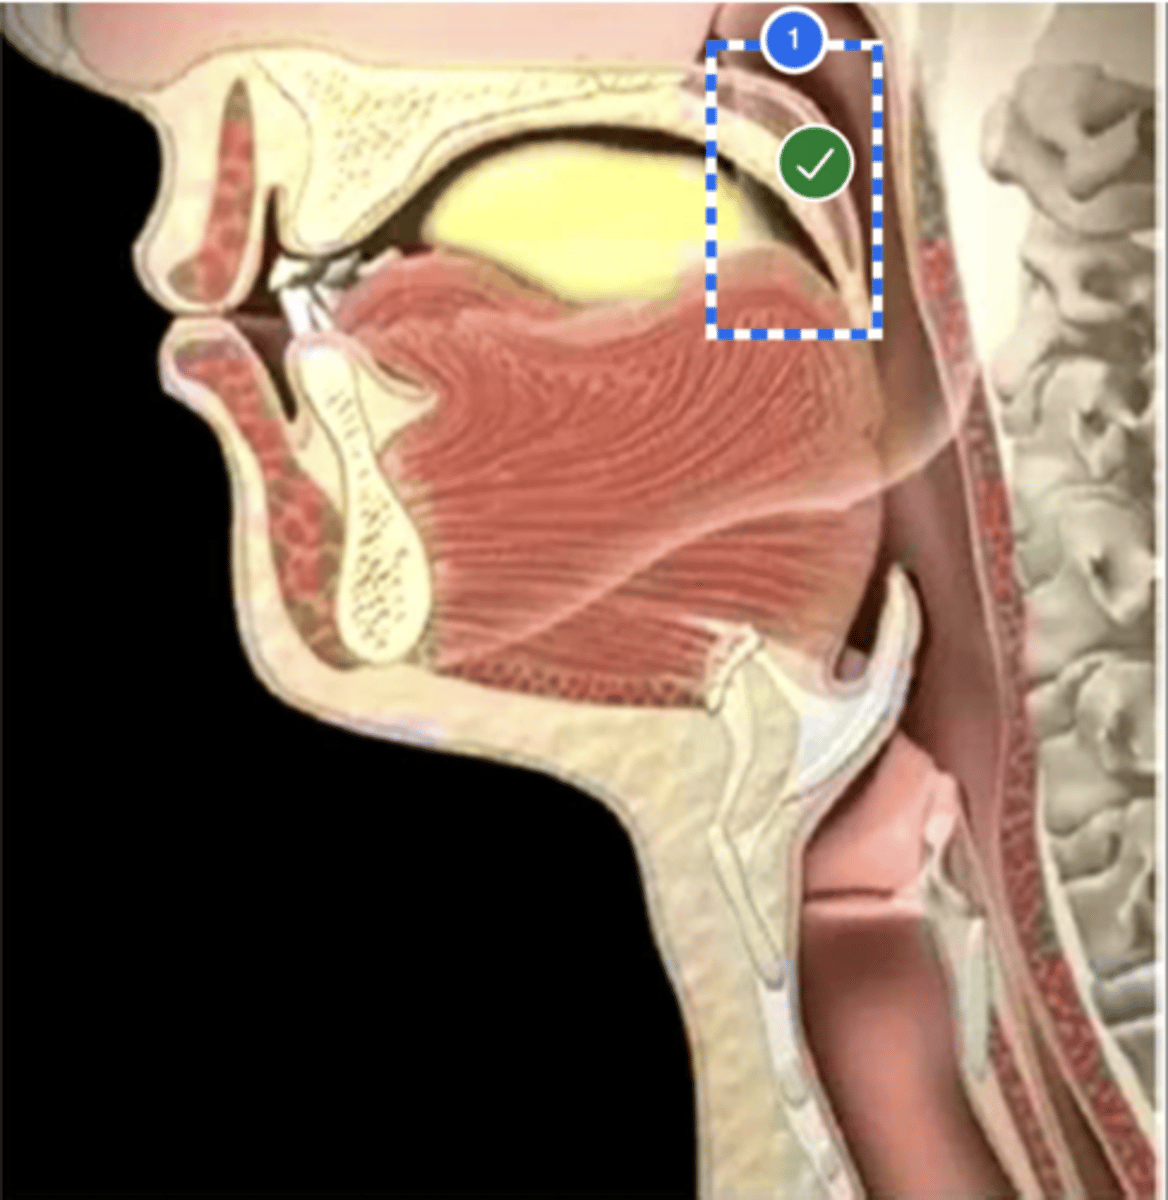

Label Nasopharynx (lateral view)

Label Nasal cavity (lateral view)

Label oropharynx (lateral view)

Label hypopharynx/ hylolarynx

Label tongue (lateral view)

Label soft velum/ palate (lateral view)

Label hard palate (lateral view)

Label mandible (lateral view)

Label base of tongue (lateral view)

label hyoid bone (lateral view)

Label epiglottis (lateral view)

label Line of true vocal folds (lateral view)

label Thyroid cartilage (anteriorly) (lateral view)

Label posterior cricoid (lateral view)

Label esophagus (lateral view)